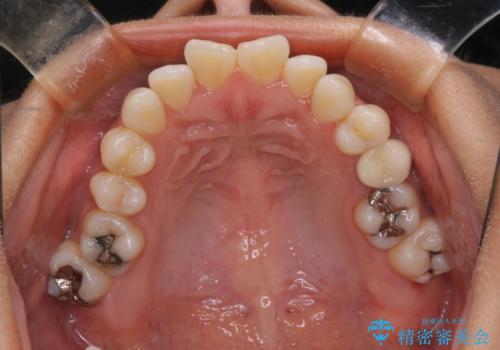

- 開咬を主訴に来院されました。前歯部に開咬、右側大臼歯部にクロスバイトが認められます。ワイヤー矯正の審美装置で治療し、ゴム掛けを行いながら噛み合わせを改善しました。

主訴である開咬と右側大臼歯部クロスバイトを改善でき、しっかりと噛むことができるようになりました。